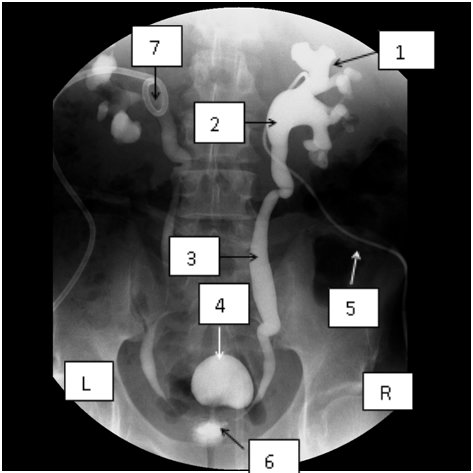

The image below shows the final image after I carried out bilateral percutaneous nephrostomies in a man with bladder outlet obstruction due to prostate cancer.

Key to the image: 1 = Right renal calyx; 2 = Right renal pelvis; 3 = Right ureter; 4 = Urinary bladder; 5 = Pigtail catheter in right renal pelvis; 6 = Narrow prostatic urethra due to prostate cancer; 7 = Pigtail catheter in the left renal pelvis. Observe that the obstruction of the left structures is less severe than the obstruction on the right. The patient was prone for the procedure, hence the seeming switching of his sides.